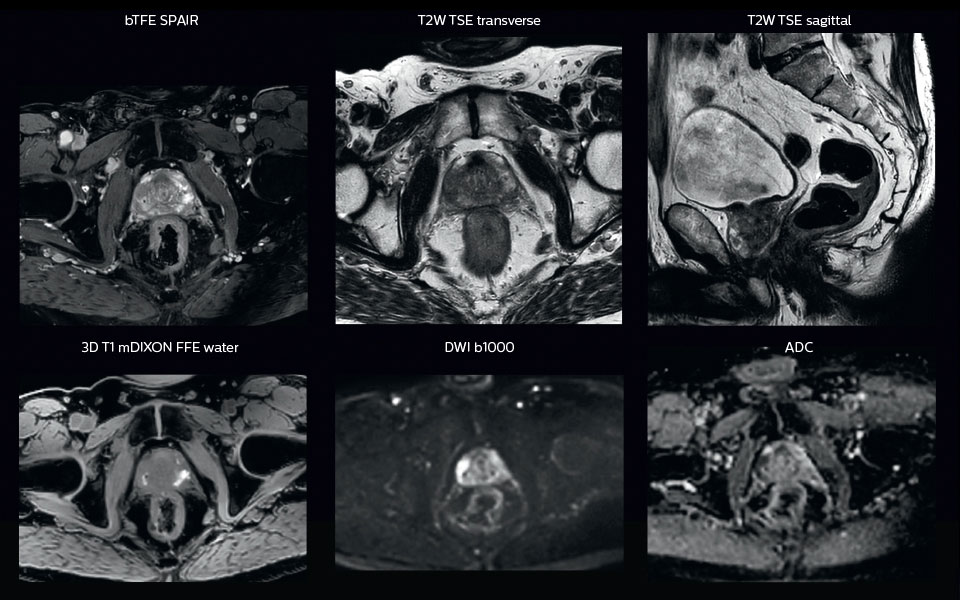

MRI is capable of visualizing the prostate and the surrounding organs such as rectum, penile bulb, bladder, the apex and seminal vesicles, as well as visualizing intra-prostatic lesions [2,4].

“All our patients undergo an MRI exam – along with CT – before radiotherapy of the prostate,” says Dr. Philippens. “For prostate delineation, we are scanning a balanced TFE with fat suppression. We can also see the gold fiducial markers in these images, which are used for position verification and are therefore used for registration to CT. For geometric accuracy of the image, we choose a 3D sequence, which is corrected for the gradient non-linearities in all directions.

“In addition to helping in delineation of the prostate, MRI also helps in visualizing the lesions inside the prostate, which may not be possible in CT.

“When we can visualize intraprostatic lesions, the radiation therapist can then plan to boost them, giving a higher dose to those lesions instead of giving a uniform dose to the whole prostate, in the hope to better treat the patient and have less risk of recurrent tumors. However, this is not yet clinical routine. For visualizing the lesions, we not only use anatomical, T2-weighted imaging, but also diffusion weighted MRI and dynamic contrast- enhanced MRI."

Visualizing critical structures with MRI before prostate radiation therapy

A 63-year-old patient with prostate cancer, cT3bNxM, Gleason 7, underwent MRI on Ingenia 3.0T MR-RT before radiation therapy.

Intraprostatic lesions are visible on the bTFE MR image, but not on the CT image. MRI shows excellent soft-tissue contrast for the visualization of critical structures like the rectum and penile bulb.